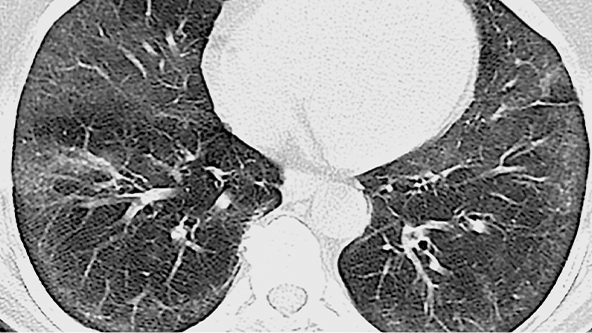

FPI – MODEL UIP

Exemplu de model IPF UIP pe HRCT

Recomandările ATS/ERS/JRS/ALAT menționează că FPI poate fi diagnosticată cu încredere dacă evaluarea clinică a pacientului indică FPI și HRCT arată un model UIP cert sau probabil (recomandare de biopsie condiționată)2